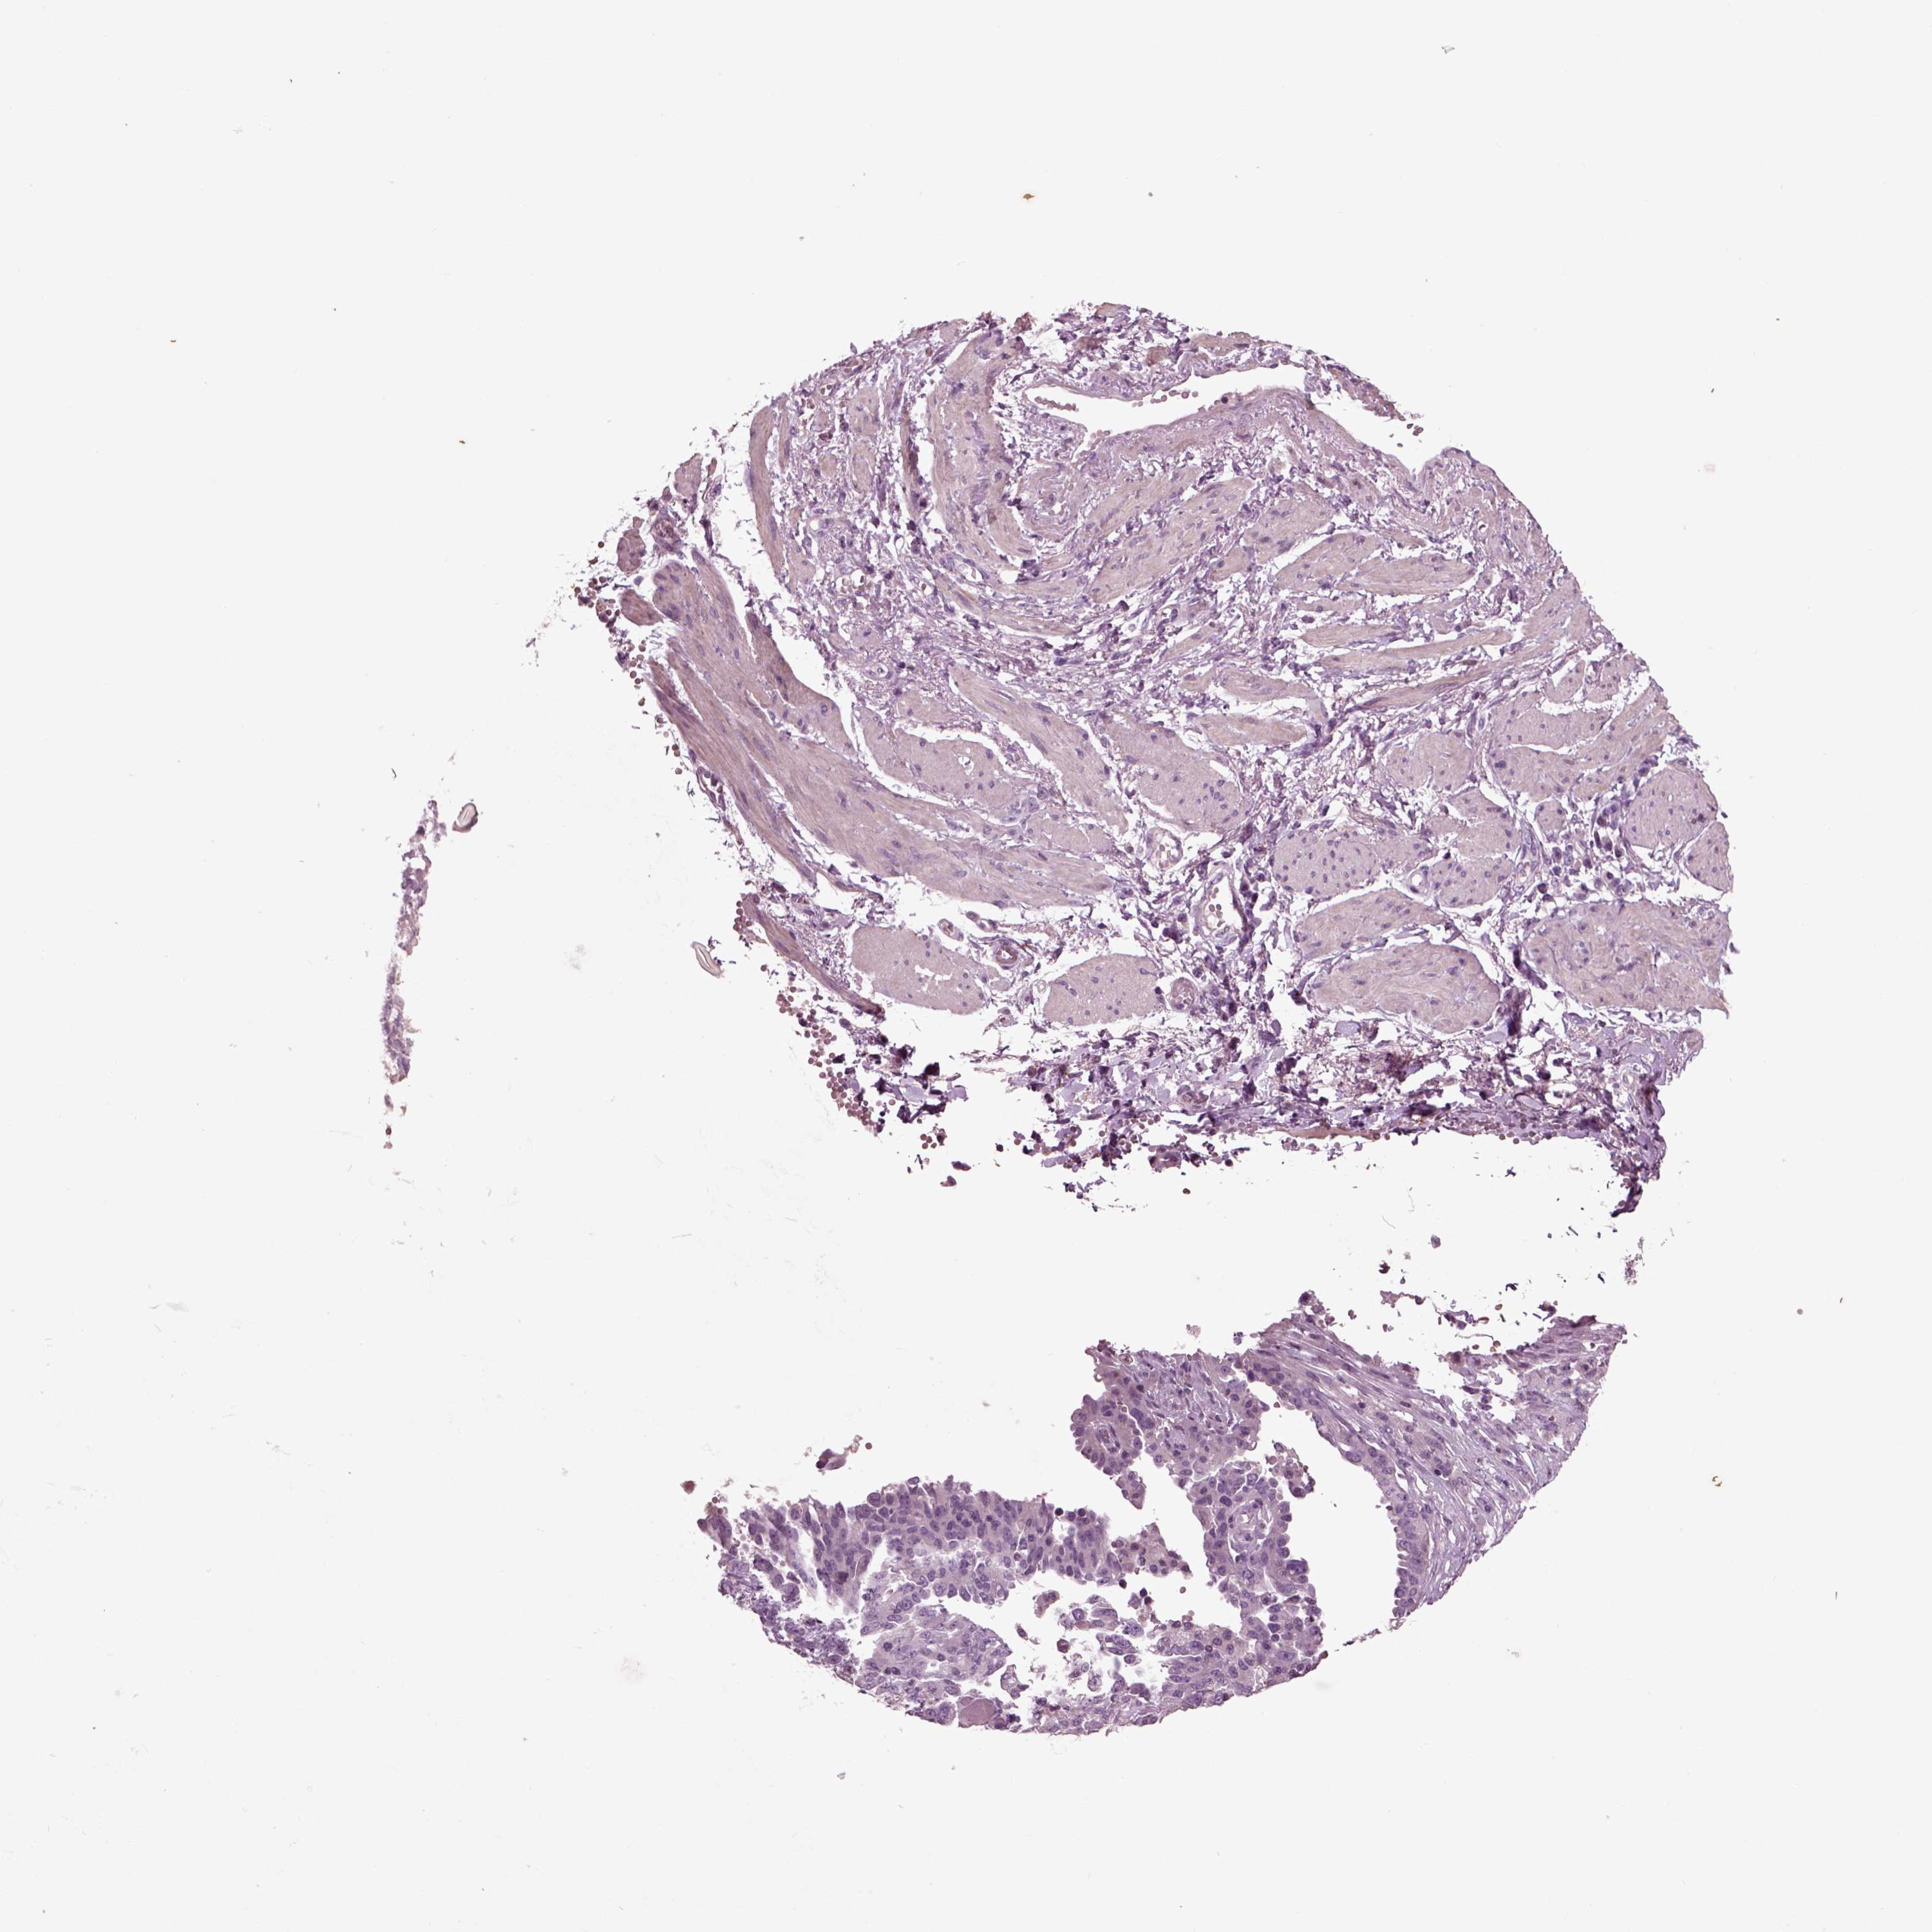

OVARIAN CANCER - Protein expressioni

A mouse-over function shows sample information and annotation data. Click on an image to view it in a full screen mode. Samples can be filtered based on level of antibody staining by selecting one or several of the following categories: high, medium, low and not detected. The assay and annotation is described here.

Note that samples used for immunohistochemistry by the Human Protein Atlas do not correspond to samples in the TCGA dataset.

Antibody stainingi

Antibody staining in the annotated cell types in the current human tissue is reported as not detected, low, medium, or high, based on conventional immunohistochemistry profiling in selected tissues. This score is based on the combination of the staining intensity and fraction of stained cells.

Each image is clickable and will lead to virtual microscopy that enables deeper exploration of all samples and also displays staining intensity scores, fraction scores and subcellular localization as well as patient and tissue information for each sample.

Antibody HPA008759

Antibody HPA012602

Antibody CAB009403

Cystadenocarcinoma, serous, NOS

Cystadenocarcinoma, mucinous, NOS

Carcinoma, endometroid